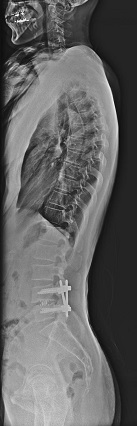

一般撮影

単純X線撮影は一般的に「レントゲン」といわれている検査です。主に胸部・腹部・骨格系の撮影を行います。全ての撮影室で最新のFPD(FPD:Flat Panel Detector)を使用しており、従来よりも被ばく線量が少なく、鮮明な画像を提供しています

• 全脊椎画像